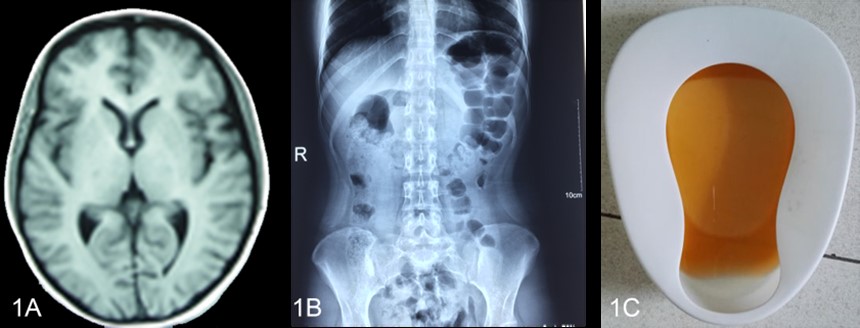

先證者2016年4月開始發(fā)。群蠖嗉乙皆赫鋃銜拔賦ρ住、 “不完全腸梗阻”、“癲癇”,并伴有低鈉血癥、低鉀血癥、高膽紅素血癥、持續(xù)性的下肢無(wú)力和疼痛,竇性心動(dòng)過(guò)速,高血壓、貧血、肝損傷,胰酶升高。在住院期間,曾排出棕色尿液促進(jìn)了對(duì)AIP的診斷。最終,尿PBG陽(yáng)性和尿鉛陰性確認(rèn)了AIP。

A 頭顱MRI顯示正常 B腹部平片示腸脹氣 C 棕色尿液

圖1-1 先證者發(fā)作的臨床資料